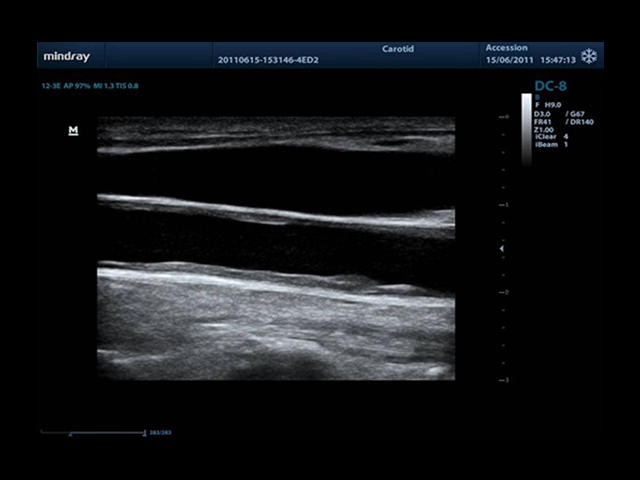

• Auto IMT Package - измерения и анализ толщины комплекса интима-медиа (КИМ) сонной артерии.

• Vascular package - предустановленные параметры, аннотации, маркеры, программы измерений для ангиологии, включая транскраниальные исследования

• Линейный ультразвуковой датчик Mindray L12-3E

• Линейный датчик Mindray L14-6WE

• Линейный датчик Mindray L7-3E